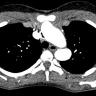

Aortic arch anomalies